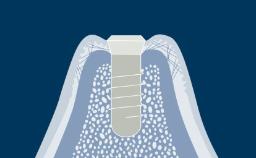

Introduction to Implant Dentistry

Tissue Integration of Dental Implants

Learning Module